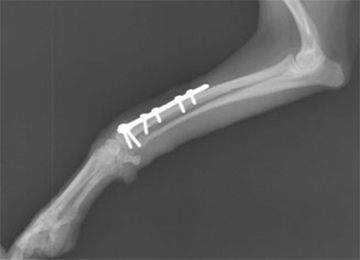

LCPプレートで骨折手術を行った症例のレントゲン写真

橈尺骨の遠位端で骨折しており、通常のプレートやピンの整復では強度の不安があります。また、犬の性格が落ち着きない子なので、この症例にはこの手術は最適でした。